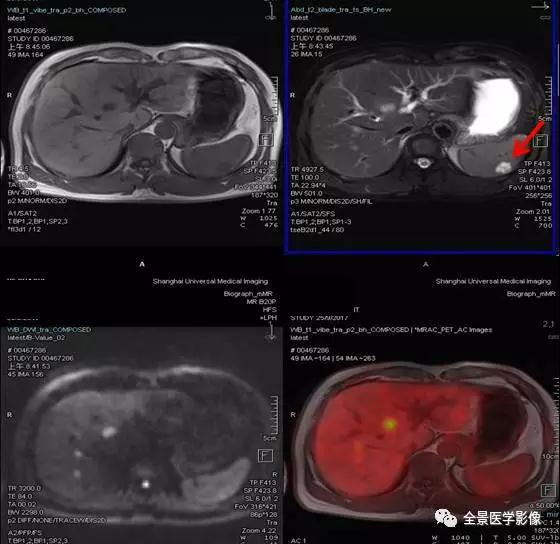

PET/MRI

脾脏

血管瘤

◆ 案例:青年男性,无不适主诉。脾脏可见一类圆形异常信号灶,长径约 1.0 cm,FDG 无代谢,考虑为脾脏血管瘤。

点评:

脾脏血管瘤属于脾脏良性肿瘤,发生基础与肝脏血管瘤相似,生长缓慢,通常都是偶然发现,此例血管瘤仅 1.0 cm,不需要外科处理,B 超定期复查即可。

淋巴管瘤

◆ 案例:中年男性,肝转移瘤患者。脾脏可见 1 枚异常信号灶,大小约 2.8 cm×3.6 cm,FDG 无代谢,考虑为良性病变,脾脏淋巴管瘤。

脾脏淋巴管瘤也属于脾脏良性肿瘤,系由囊性扩张的淋巴管构成,生长缓慢,病灶小,无临床症状者,不需要外科处理,B 超定期复查。此例病灶 FDG 无代谢,PET/MR 帮助排除脾脏转移。